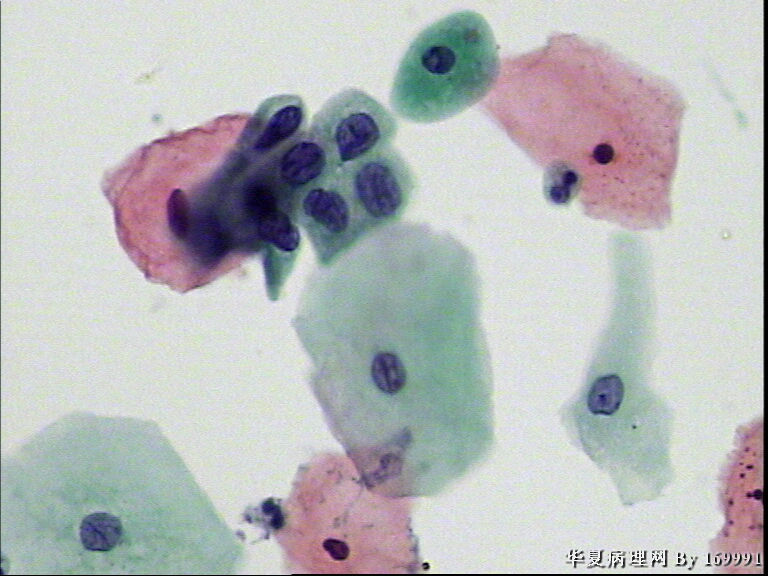

宫颈液基,患者,23岁,宫颈中糜

• 宫颈液基,患者,23岁,宫颈中糜图1

图1

我感觉报HSIL有点高了,就细胞的形态来看,核增大深染的基本上还是中层以及接近表层的细胞,结合患者年龄,我认为报LSIL更好一些。不知道对不对,请各位老师指教啦!

大家都看得不错。最高可能是CINII级,看活检了。

感觉像高级别,但患者年龄太小。ASC-H